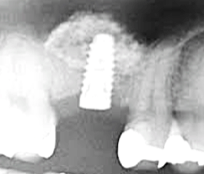

ソケットリフト法はインプラント埋入部から上顎洞底粘膜を引き上げて

その部分に骨の代価となる骨補填材を隙間に填入していく方法です。

この場合、インプラントは骨内に完全に埋入されるものではなく、初期固定が弱くなることが多いため、

(上顎骨は下顎骨に比較して弱いということや直接骨と接触するインプラント面積が少ないことなど)

通常のインプラント手術と比較して骨結合を待つ時間が長くなることが特徴ですが、